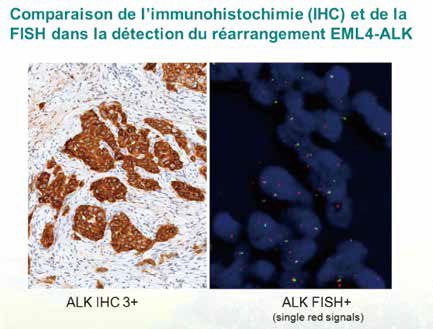

先IHC筛查后FISH确证的ALK检查策略更佳

先IHC筛查后FISH确证的ALK检查策略更佳

荷兰研究者Thunnissen等报告,在非小细胞肺癌(NSCLC)中,ALK IHC + FISH-的情况罕见,且提示个体治疗的结局更差。相对目前指南关于ALK IHC等效于ALK FISH的观点,先应用I…